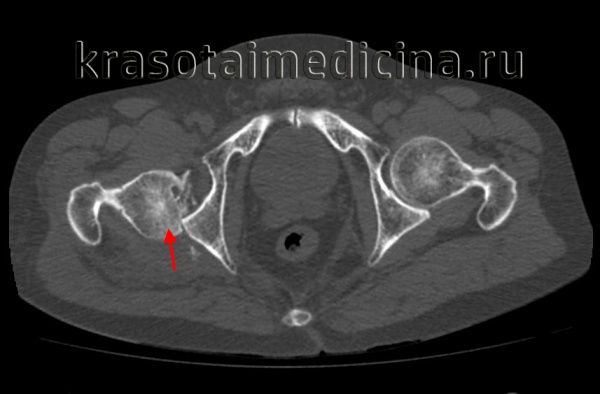

КТ таза. 3D-реконструкция. Красная стрелка – вывихнутая головка бедренной кости, синяя стрелка – «пустая» вертлужная впадина.

Рентгенография в дополнительных проекциях помогает оценить проксимальный сегмент бедренной кости с целью исключения переломов головки и шейки бедра. После вправления вывиха необходимо провести КТ, чтобы оценить результаты вправления, уточнить целостность вертлужной впадины и исключить наличие костных фрагментов в полости сустава. Вывихи изредка сопровождаются переломами головки бедра, которые должны быть соответствующим образом выявлены и устранены.